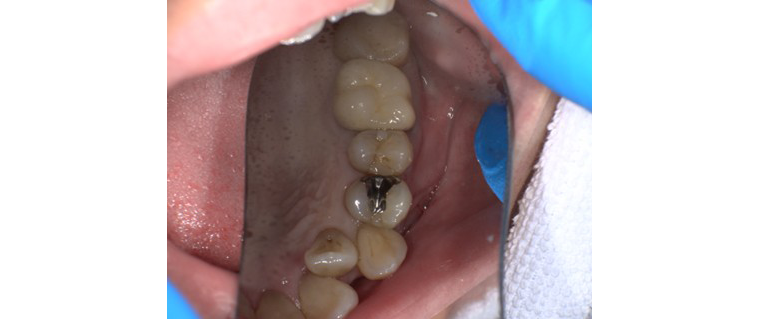

【症例No.3】左下奥歯 セラミックインレー修復/30代女性

Before

After

主訴

銀歯が目立つのが気になる、自然な色でやり直したい

治療内容

セラミックインレー(e.max使用)

治療期間・回数

2回(約1週間)

費用

54,900円(税込)

リスク・副作用

治療では古い詰め物を除去するため、神経に近い箇所を触れる場合があります。そのため、一時的な知覚過敏や、噛み合わせの強さにより欠けたり脱離するリスクがあります。

セラミックインレーは自然な色味とフィット感に優れ、隣の歯との調和も抜群です。治療後は見た目の違和感がなく、機能面でも問題なく使用いただけています。